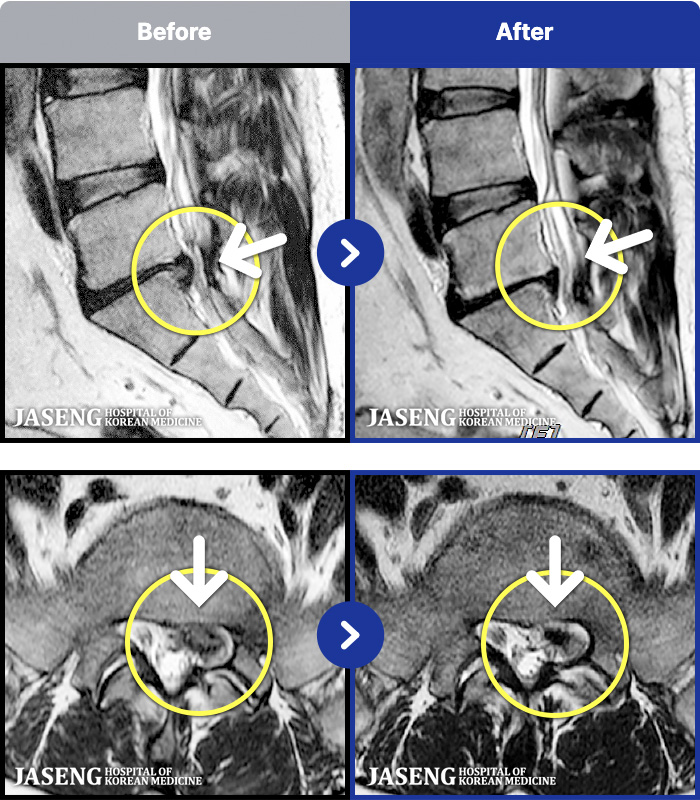

MRI ġ

1,299 MRI ũ ʸ Ȯϼ.